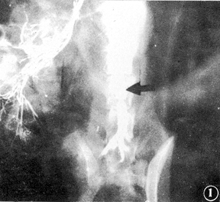

经大体解剖及动脉造影检查两组移植物的通畅、阻塞、狭窄的结果相一致(图1,附表)。AJV组6个月内的通畅率达95.2%,HUV组6个月内的通畅率为87.5%,两组差异无显著意义(P>0.05)。

图1 腹主动脉造影,HUV移植后6个月,移植段静脉通畅(箭头)